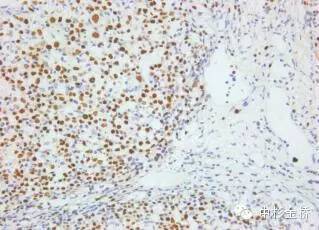

圖為EBER原位雜交染色DBA顯色,蘇木素復(fù)染

EBER是EB病毒編碼的小RNA,在EB病毒感染的細(xì)胞核中高拷貝存在。根據(jù)EBER的序列設(shè)計(jì)的EBER RNA探針,可以用于石蠟切片,具有較高的特異性和靈敏度,該試劑盒廣泛應(yīng)用于美國(guó)、歐盟等各國(guó)。

- RNA探針,定位準(zhǔn)確,敏感性強(qiáng)